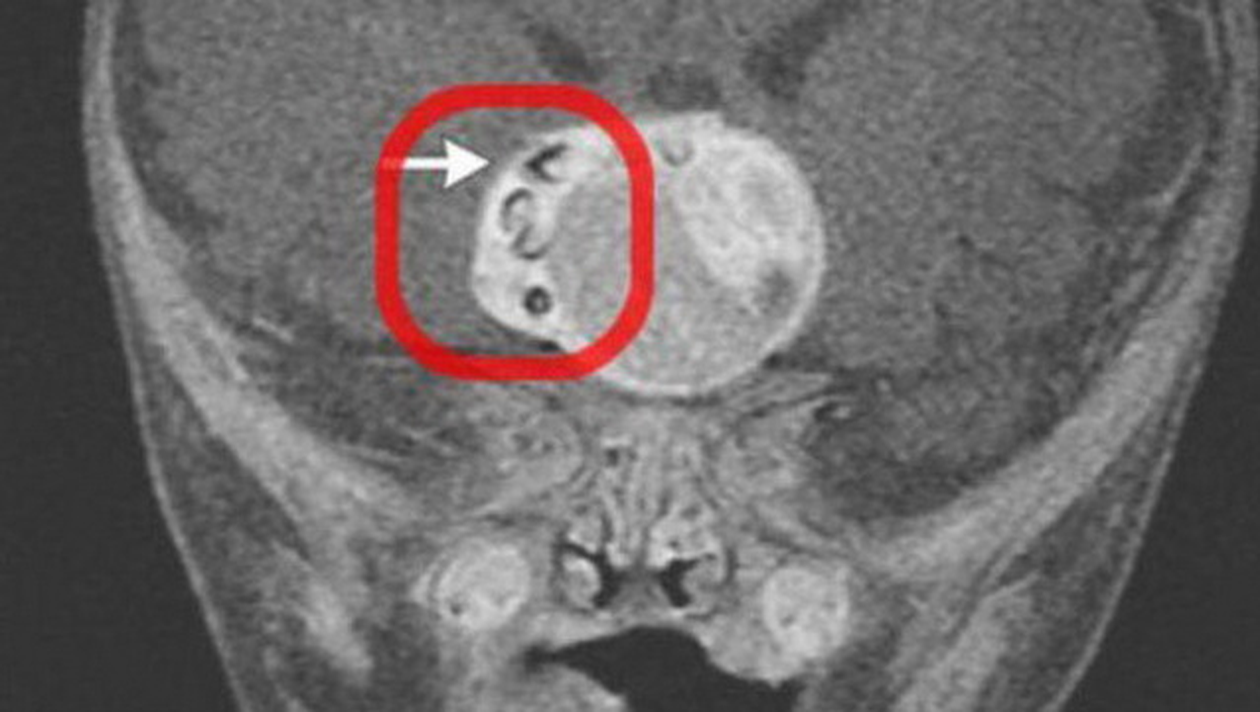

O echipa de doctori a facut o descoperire socanta. Au gasit un dinte care a crescut in creierul unui bebelus de doar 4 luni.

Forma rara de cancer a fost descoperita in creierul unui copilas din Maryland (SUA), anul trecut. Ciudata descoperire a fost publicata intr-o revista medicala.

Dintele crescuse intr-o tumora numita adamantinomatous craniopharyngioma.

Tumora avea 4.1 cm latime, 4 cm lungime si 3.5 cm inaltime.